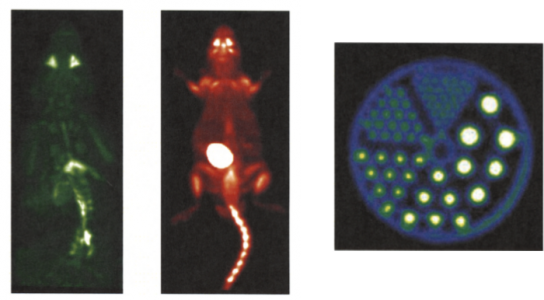

| ABSTRACT | Introduction: Simultaneous in-vivo imaging of several biological processes may improve oncological, neurological and cardiovascular studies by providing complementary information obtained under the same exact conditions and coregistered in space and time. Standard PET imaging does not allow multiplexed acquisitions, as all annihilation photons have the same energy. We developed a technique called multiplexed PET (mPET), which uses a tracer labelled with a pure positron emitter (such as 18 F, 13 N, 11 C), and a tracer labeled with a positrongamma emitter (such as 124 I, 76 Br, 82 Rb, 86 Y). Positrongamma emitters generate a significant number of triplecoincidences , which allows them to be differentiated from the standard PET radionuclides . In this work, we evaluated the performance of mPET using phantom and animal experiments. |